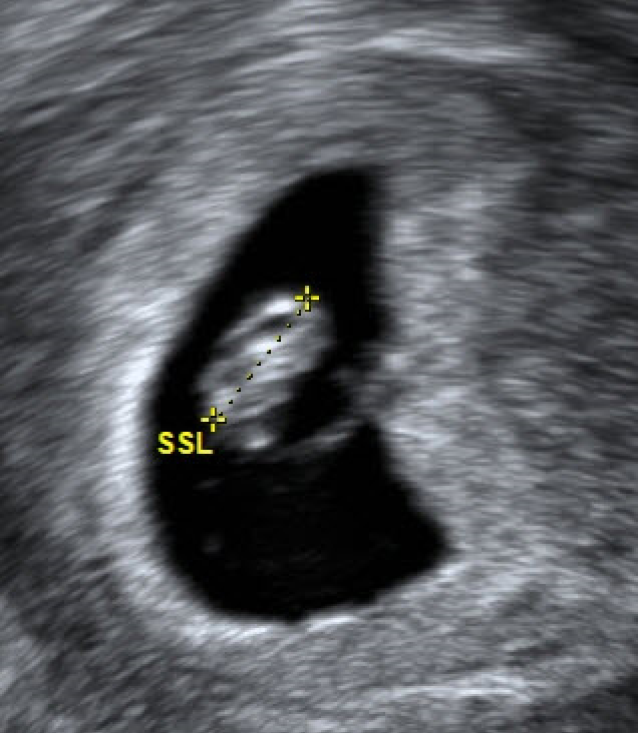

Abb. 2

Erste Zeichen eines Embryos mit 2,2 mm Länge, direkt dem Dottersack anliegend (6 + 0 SSW nach Pexsters)

Hauptfehlerquelle ist die Messung des Embryos mit dem Dottersack, hier kann durch Einbeziehung des Dottersacks in die Messstrecke das tatsächliche Gestationsalter um bis zu eine Woche überschätzt werden (Abb. 2).